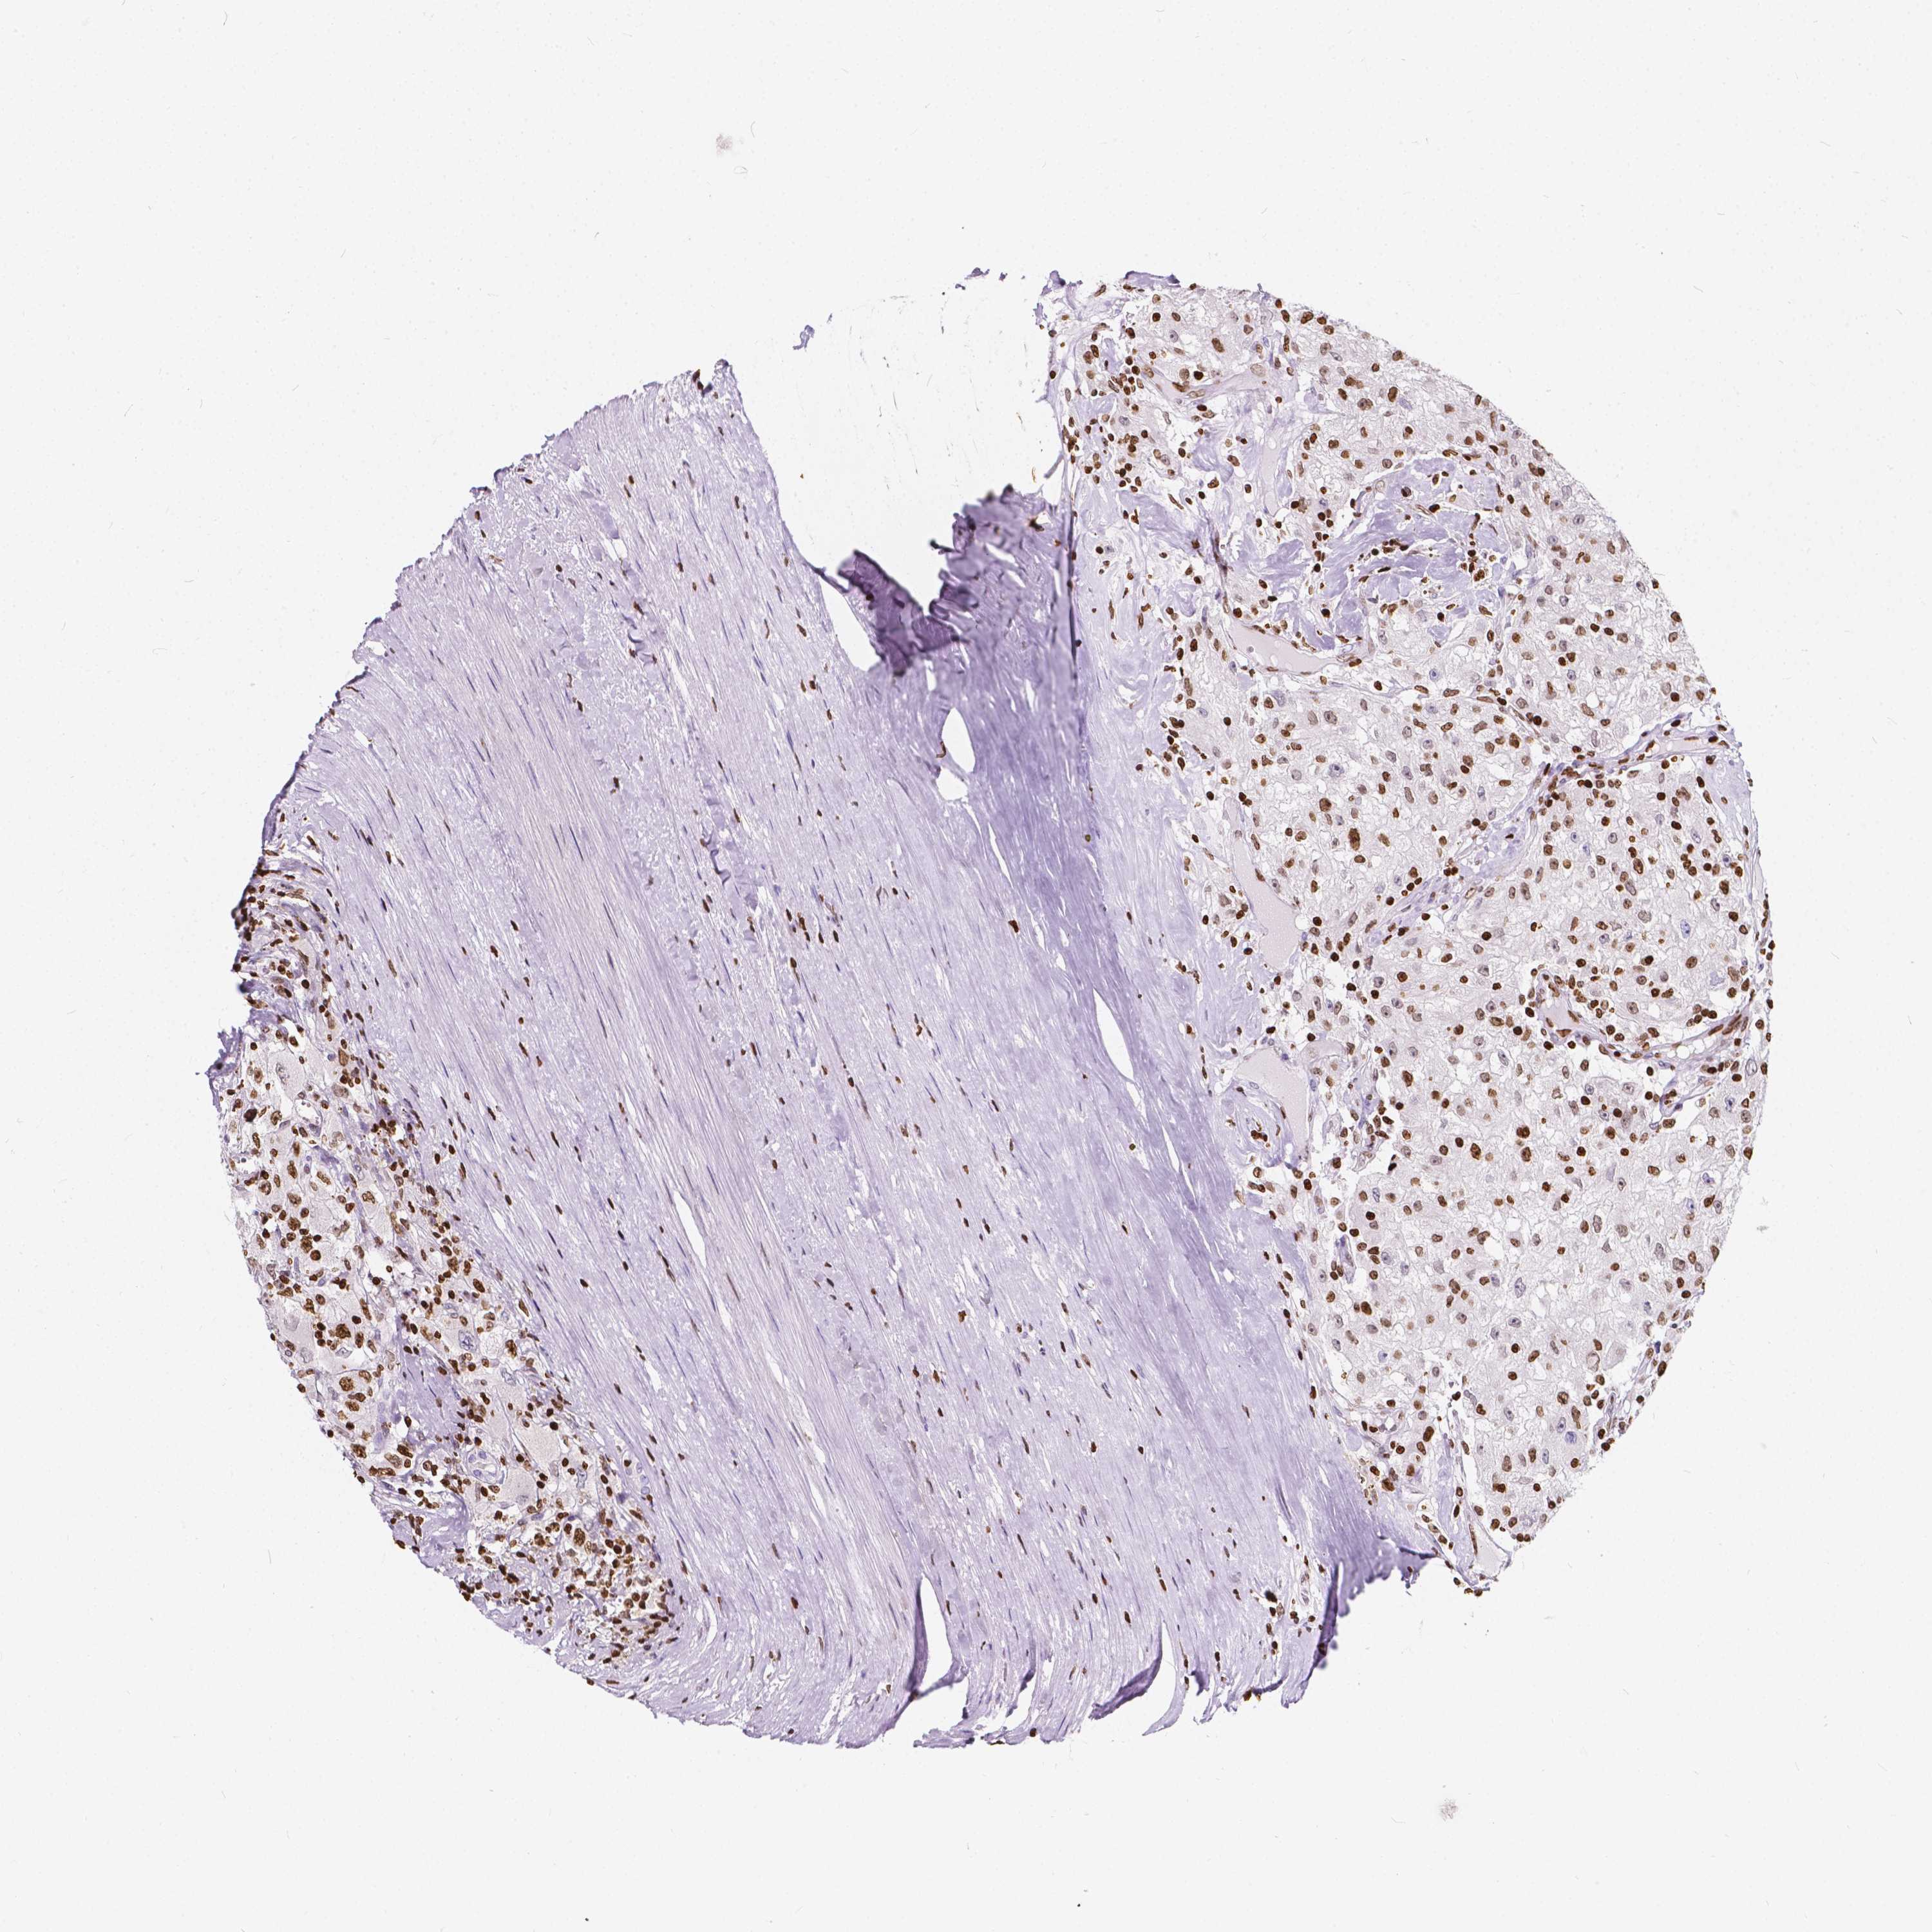

CANCER RENAL CANCER Show tissue menu

KICH TCGA KIRC TCGA KIRC VALIDATION KIRP TCGA PROTEIN RCC CPTAC PROTEIN EXPRESSION